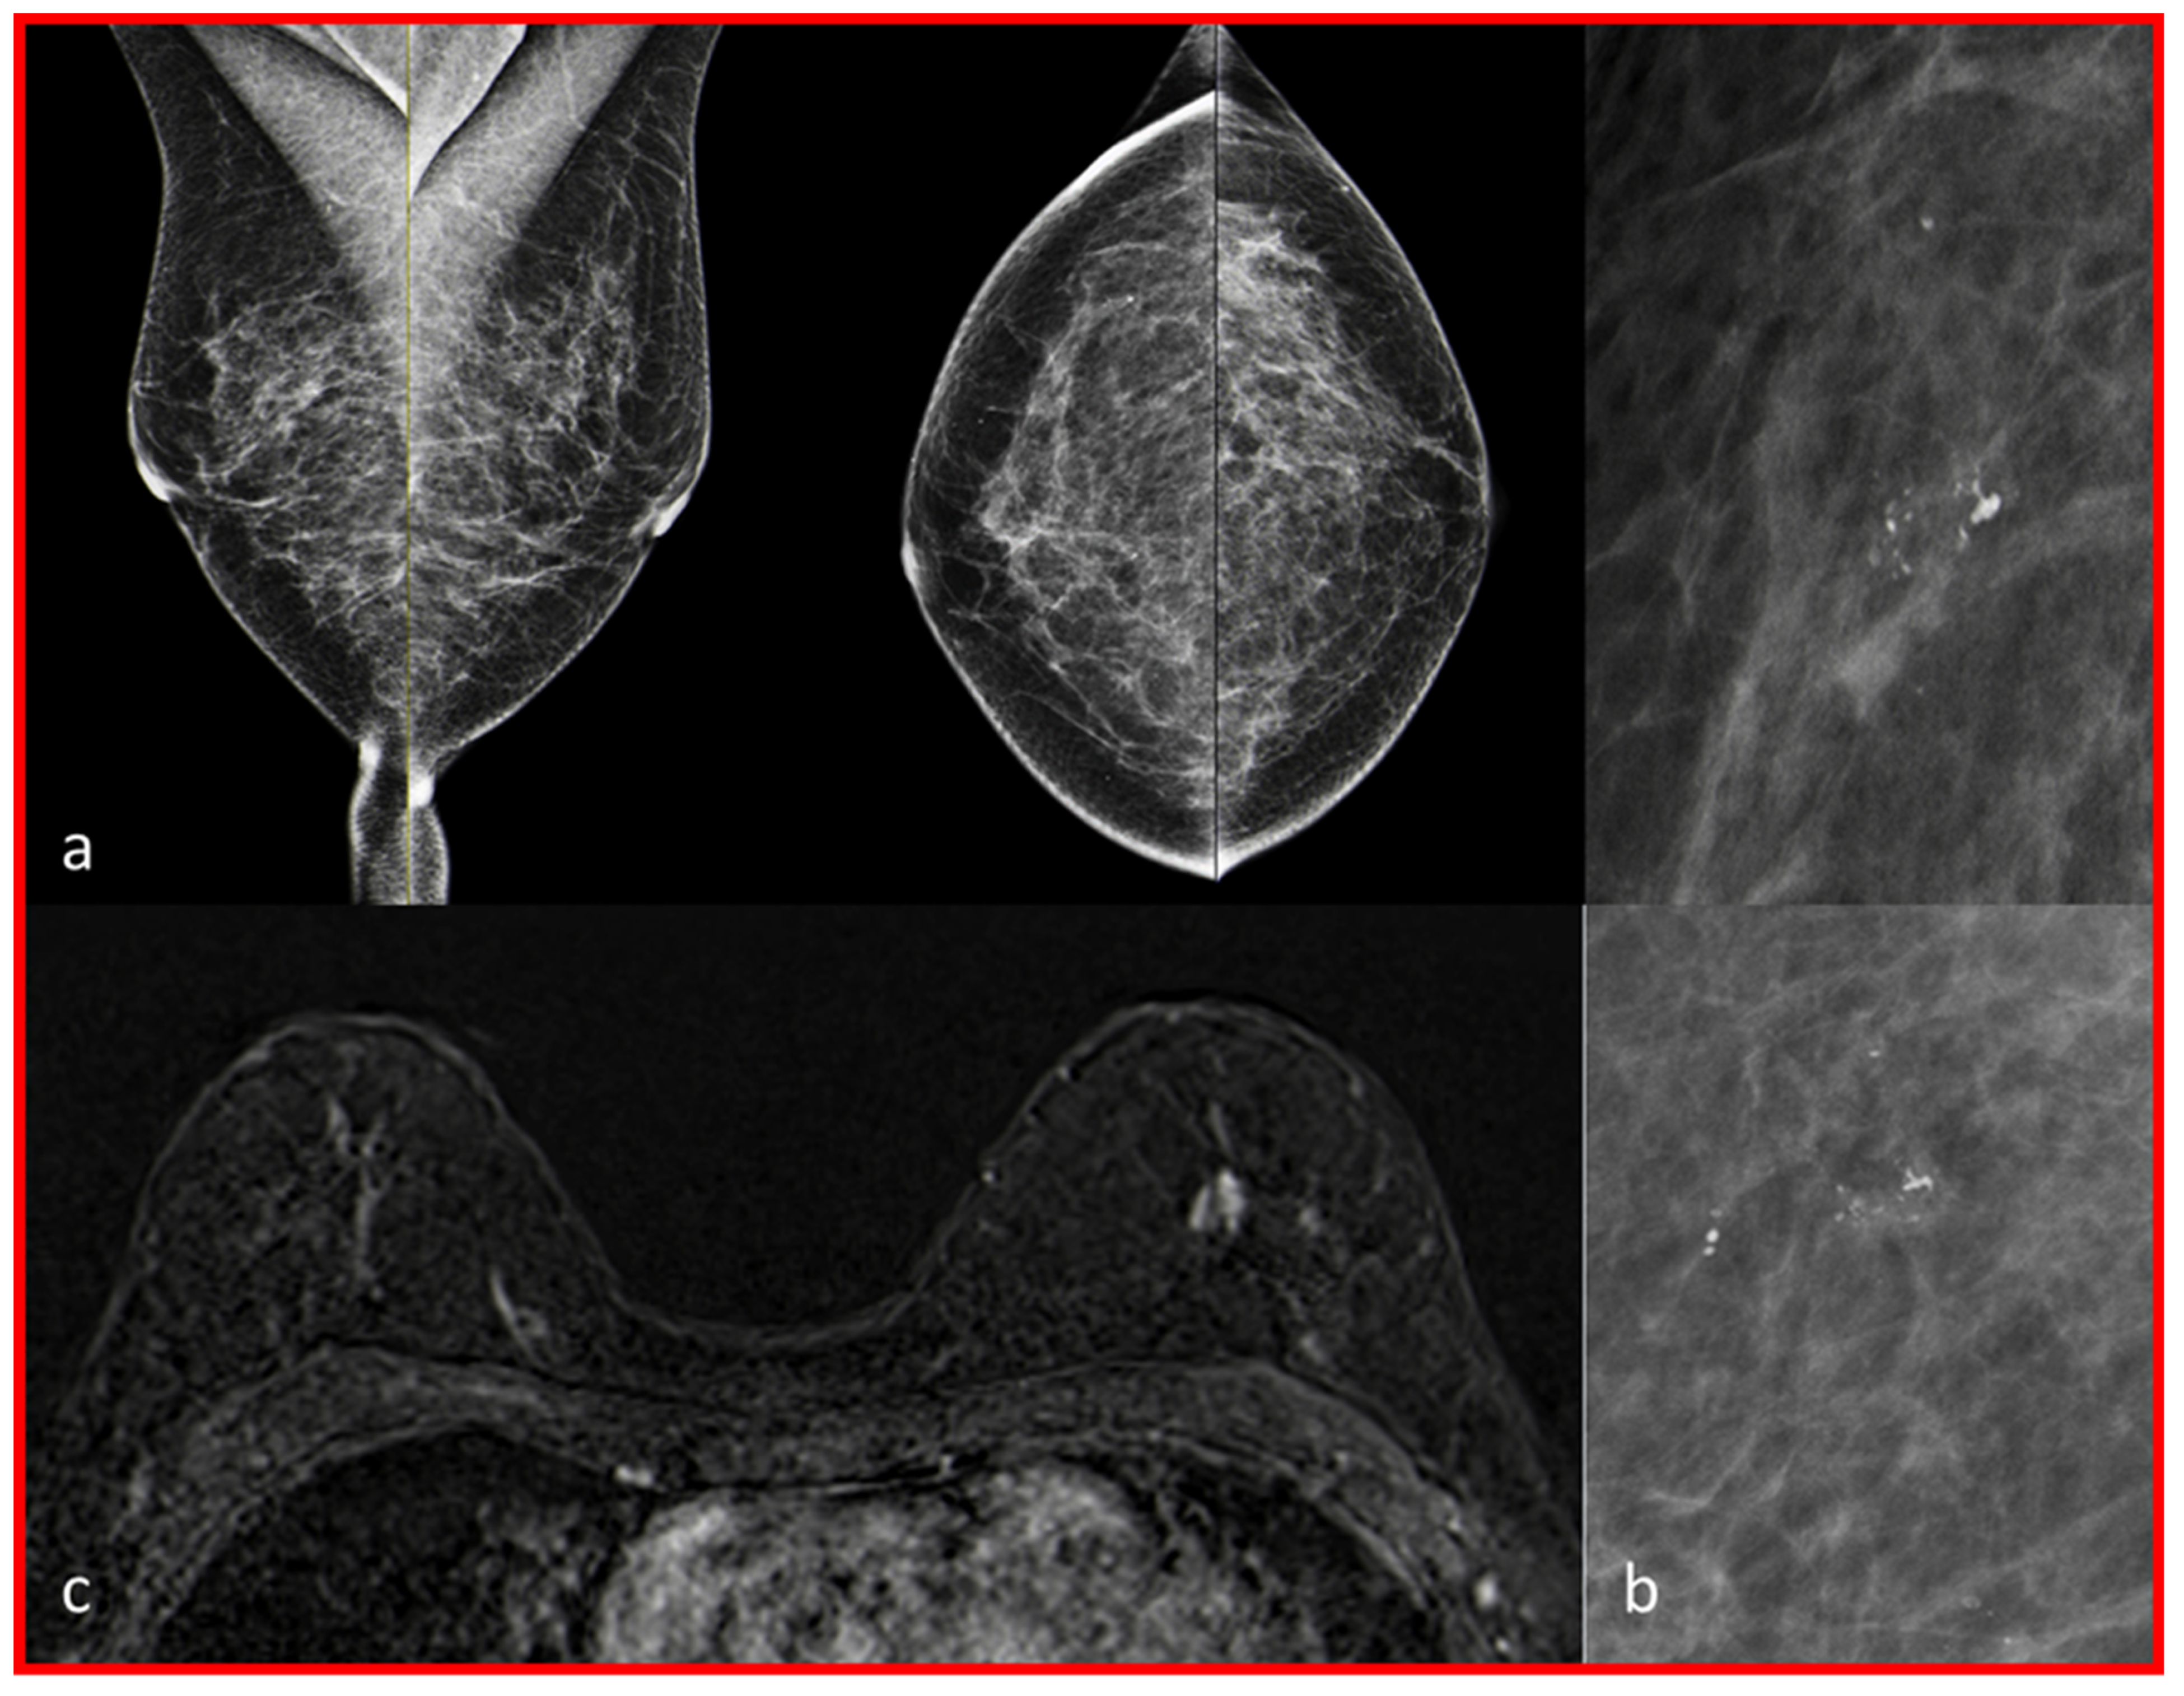

| 1 | I | Mild | Mass, circumscribed, oval | c | Localization outside the MG coverage near the chest wall | Core biopsy guided by ultrasound | 1.4 cm G1 NST/ER 90%, PR 30%, Ki-67 5%, HER2 negative/pT1c pN0 L0 V0 Pn1 G1 |

| 2 | II | Moderate | NME, segmental, heterogeneous | b | No MCs | MRI-guided vacuum-assisted biopsy | 13.4 cm low-grade DCIS |

| 3 | II | Moderate | NME, linear | b | Unilateral MCs in different position | MRI-guided vacuum-assisted biopsy | 0.6 cm G1 tubular carcinoma/ER 90%, PR 30%, KI-67 10%, HER2 negative/pT1b pN0 L0 V0 Pn0 G1 associated with 3.2 cm low-grade DCIS |

| 4 | I | Minimal | Mass, irregular, not circumscribed-spiculated, heterogeneous | b | Unilateral MCs in different position | Core needle biopsy | 0.5 cm G3 NST/ER 90%, PR negative, Ki-67 60%, HER2 negative/ypT0 pN0 L0 V0 Pn0 |

| 5 | II | Moderate | NME, grouped, regional | c | No MCs | Partial excision | 0.7 cm G2 NST//ER 90%, PR 40% Ki-67 20% HER2 negative/pT1b pN0 L0 V0 Pn0 G2 associated with 5.0 cm low-grade DCIS |

| 6 | I | Mild | NME, linear, heterogeneous | b | No MCs | Duct excision | Fibrocystic changes |

| 7 | I | Mild | NME, diffuse, heterogeneous | b | No MCs | Core needle biopsy guided by ultrasound | UDH |

| 8 | I | Minimal | NME, linear, homogeneous | c | Unilateral MCs in different position | Partial excision | Fibrocystic changes |

| 9 | I | Moderate | NME, focal, homogeneous | c | Unilateral MCs in different position | Partial excision | FEA |